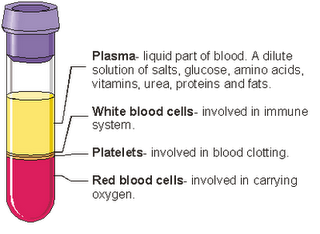

- Components of blood and their functions (Red blood cell, white blood cell, platelets and plasma (blood groups)